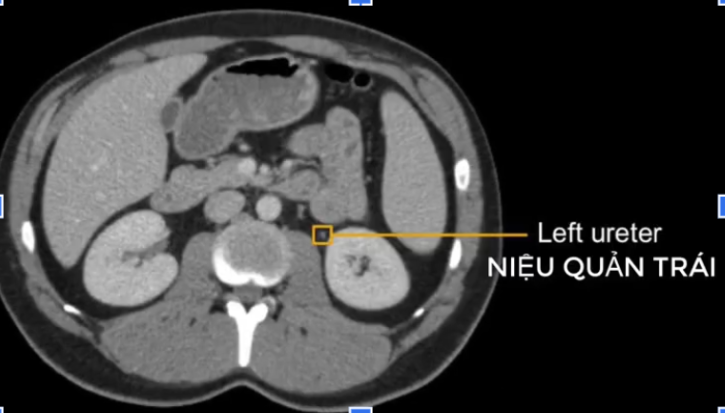

b) Niệu quản ở?